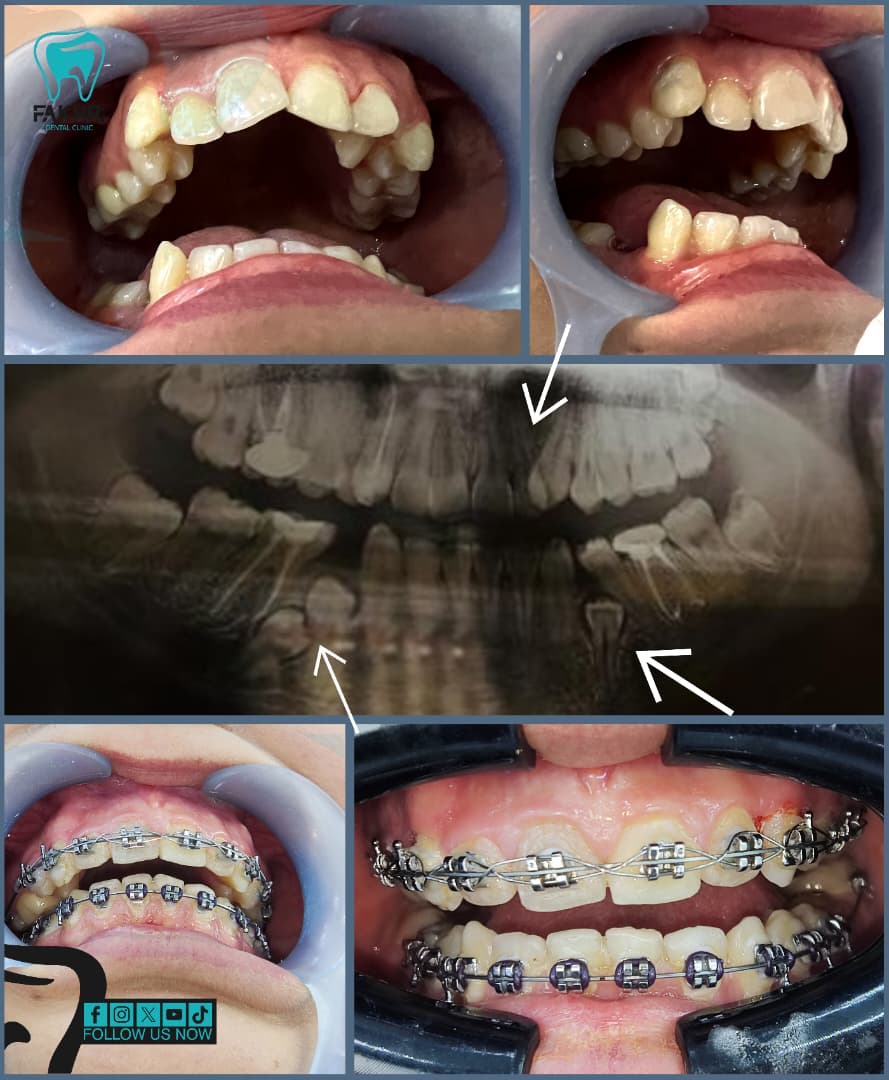

• Orthodontic Consultation and Records (Photos, X-rays, Impressions)

• Metal & Ceramic Braces

• Self-Ligating Braces